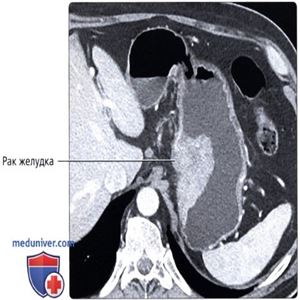

КТ с контрастированием, аксиальный срез: определяется крупное полиповидное объемное образование, растущее на малой кривизне желудка; по данным эндоскопии диагностирован рак желудка.

КТ с контрастированием, аксиальный срез: распространенное утолщение стенки желудка по ходу его малой кривизны в виде объемного образования. Хотя определение утолщения стенки при КТ может быть затруднено, в особенности, если желудок не расширен, наличие очагового утолщения стенки должно настораживать в отношении наличия злокачественного новообразования.